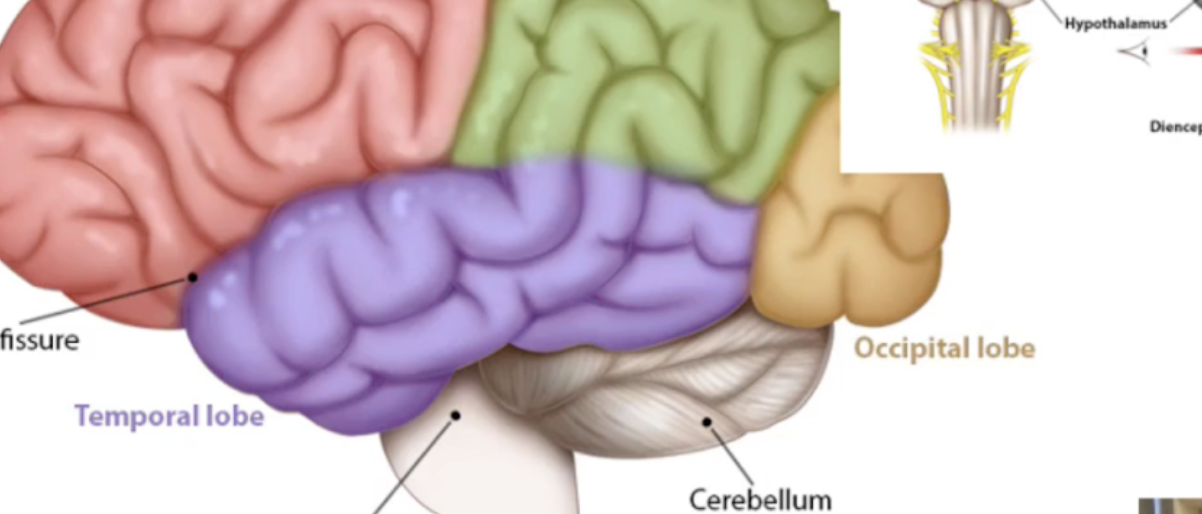

What are the ridges (folds) on the cerebrum called?

Gyrus/Gyri (Peak of the sunchip)

What are the grooves(valley) on the cerebrum called?

Sulcus/Sulci valley between the peak

Lobe function: motor speech,memory formation,personality,Emotion

Frontal Lobe

Lobe function: Somatosensory cortex(sense processing), Sensory integration, Spatial awareness

Parietal Lobe

Lobe function: Visual processing and storing visual memories (posterior side)

Occipital Lobe

Lobe functuon haering, language, smell

Temporal lobe